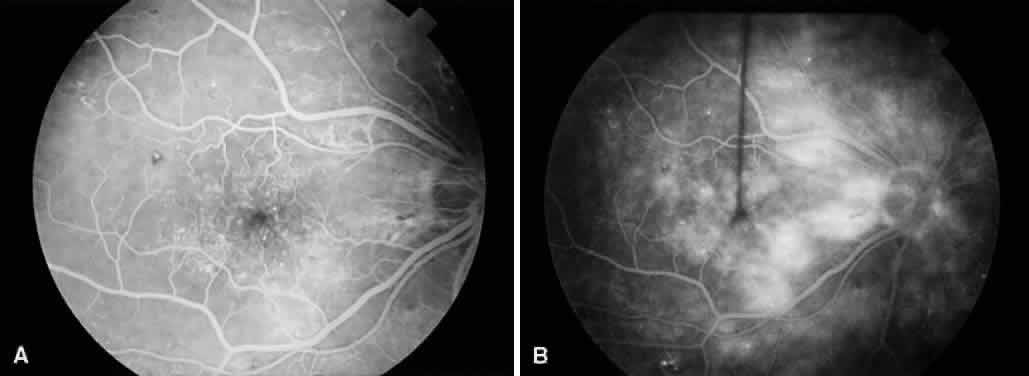

SILICONE OIL IN DIABETIC VITRECTOMY

Fig. 7. A. Preoperative fundus photograph of an eye with recurrent combined retinal detachment from proliferative diabetic retinopathy and proliferative vitreoretinopathy. B. Postoperative fundus photograph of the same eye. The retina has been successfully reattached using silicone oil tamponade.